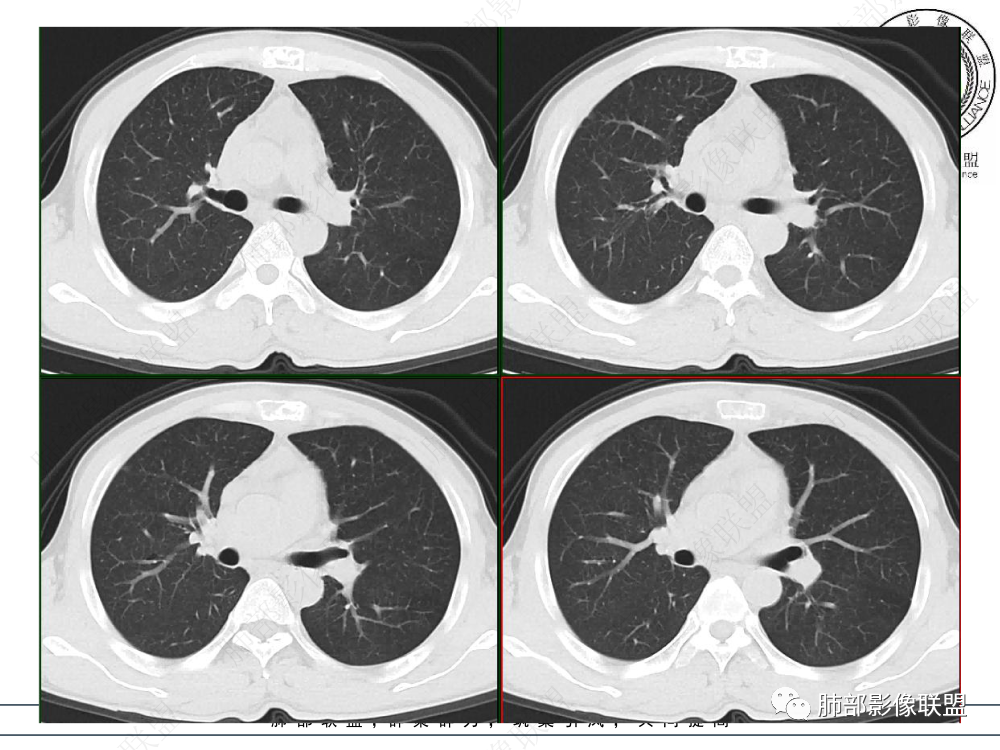

1.临床资料:中老年男性,病史较长-8个月,主诉胸痛,实验室资料:乳酸脱氢酶(LDH)升高。

2.影像表现:前上纵隔较大肿块,密度不均,形态不规则,边界不清,有结节样突起,脂肪间隙显示不清。病灶侵犯左无名静脉及上腔静脉,其中左无名静脉闭塞(胸背部侧支循环明显,亦表明回流受阻)。增强后轻中度不均强化。坏死边界欠清晰。可见心包积液,提示心包受侵犯。右侧上叶及纵隔胸膜下结节影,疑胸膜肺转移可能。胸骨柄后缘皮质不完整,疑骨质破坏(未提供骨窗及矢状位图像)。左锁骨上可见肿大淋巴结。